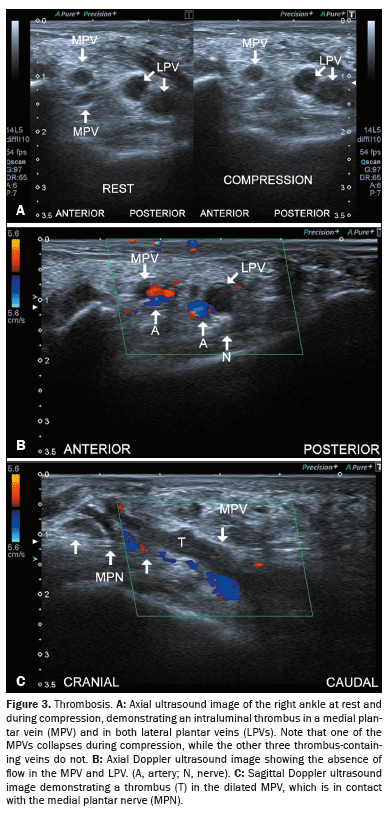

Kinking of the tibial artery

Although kinking of the tibial artery is not uncommon, only cases where the kinked artery directly impinges on or compresses the nerve are clinically relevant to TTS(1,7), as shown in Figure 4.